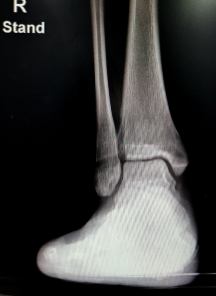

- 진단: 먼저 의사는 물리 검사, X-레이 및 MRI를 통해 인대 파열 정도를 확인합니다.